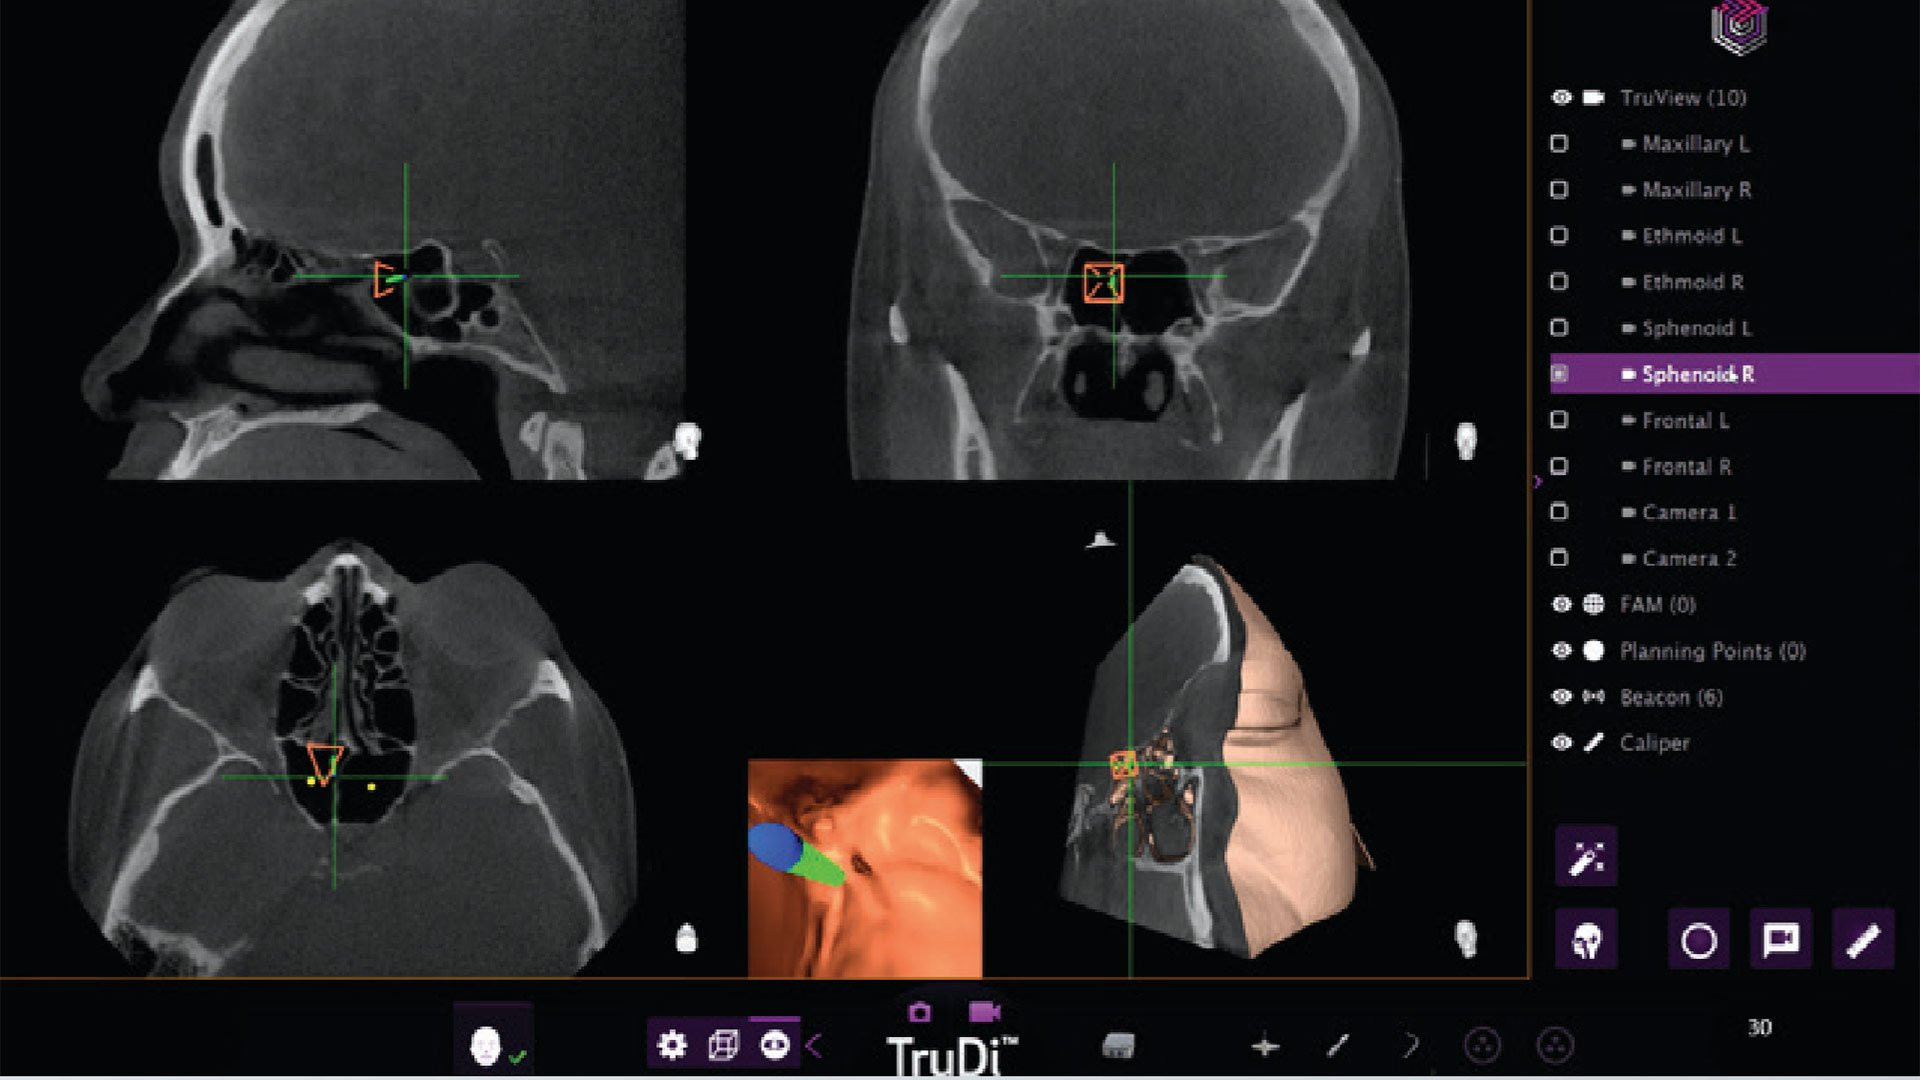

The TruDi system, designed to simplify surgical planning and provide real-time feedback during delicate sinus procedures, experienced a dramatic increase in reported malfunctions after AI algorithms were integrated. Before the AI enhancement, the device had documented eight malfunctions over three years on the market. Following the AI integration, that number jumped to at least 100 malfunctions and adverse events, according to the Reuters report.